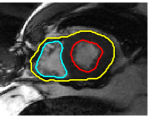

The problem above is a generalization of Horn & Schunck optical flow. Note that solving for the Horn & Schunck optical flow within each region separately does not lead to motions such that at the interface, they have equal normal components (see Figure 1), whereas the solution of (5) to be presented in subsequent sections does. Note that computing Horn & Schunck optical flow in each region requires boundary conditions (and typically they are chosen to be Neumann boundary conditions: and on ). Note that replacing these boundary conditions with the boundary constraint (6) does not specify a unique solution. Also, while Horn & Schunck optical flow computed on the whole domain naturally gives a globally smooth motion, which by default satisfies matching normals at the interface, this is not natural for the ventricles / myocardium, where different motions exist in the regions (see Figure 2), and the motions should not be smoothed across the regions.

![]() |

| image + boundary | global optical flow | our method | our method (motion decomp.) |